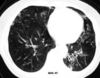

18

Q

A

Patrón intersticial reticular

19